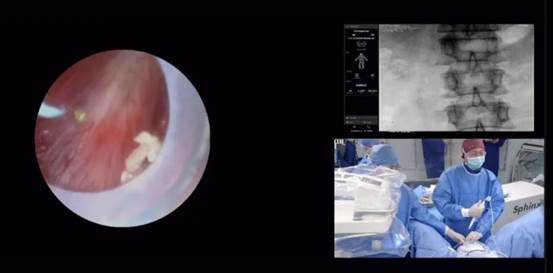

自疫情回暖后首次夏季开班就吸引了来自希腊、德国、西班牙、比利时、澳大利亚等22个欧洲及亚太国家的多位年轻泌尿科医生齐聚希腊帕特雷大学会议中心。除了干货满满的泌尿大师讲座和精彩的手术教学展示,还有手把手操作实践(Hands-on training)培训环节,医师学员分为四组轮换上手并热情投入到模拟操作f-URS碎石手术中。

瑞派旗下泌尿产品良好的操控性能,清晰的主机图像,加上强大的系统抗干扰性可帮助医生在激光碎石手术达到更佳效果。